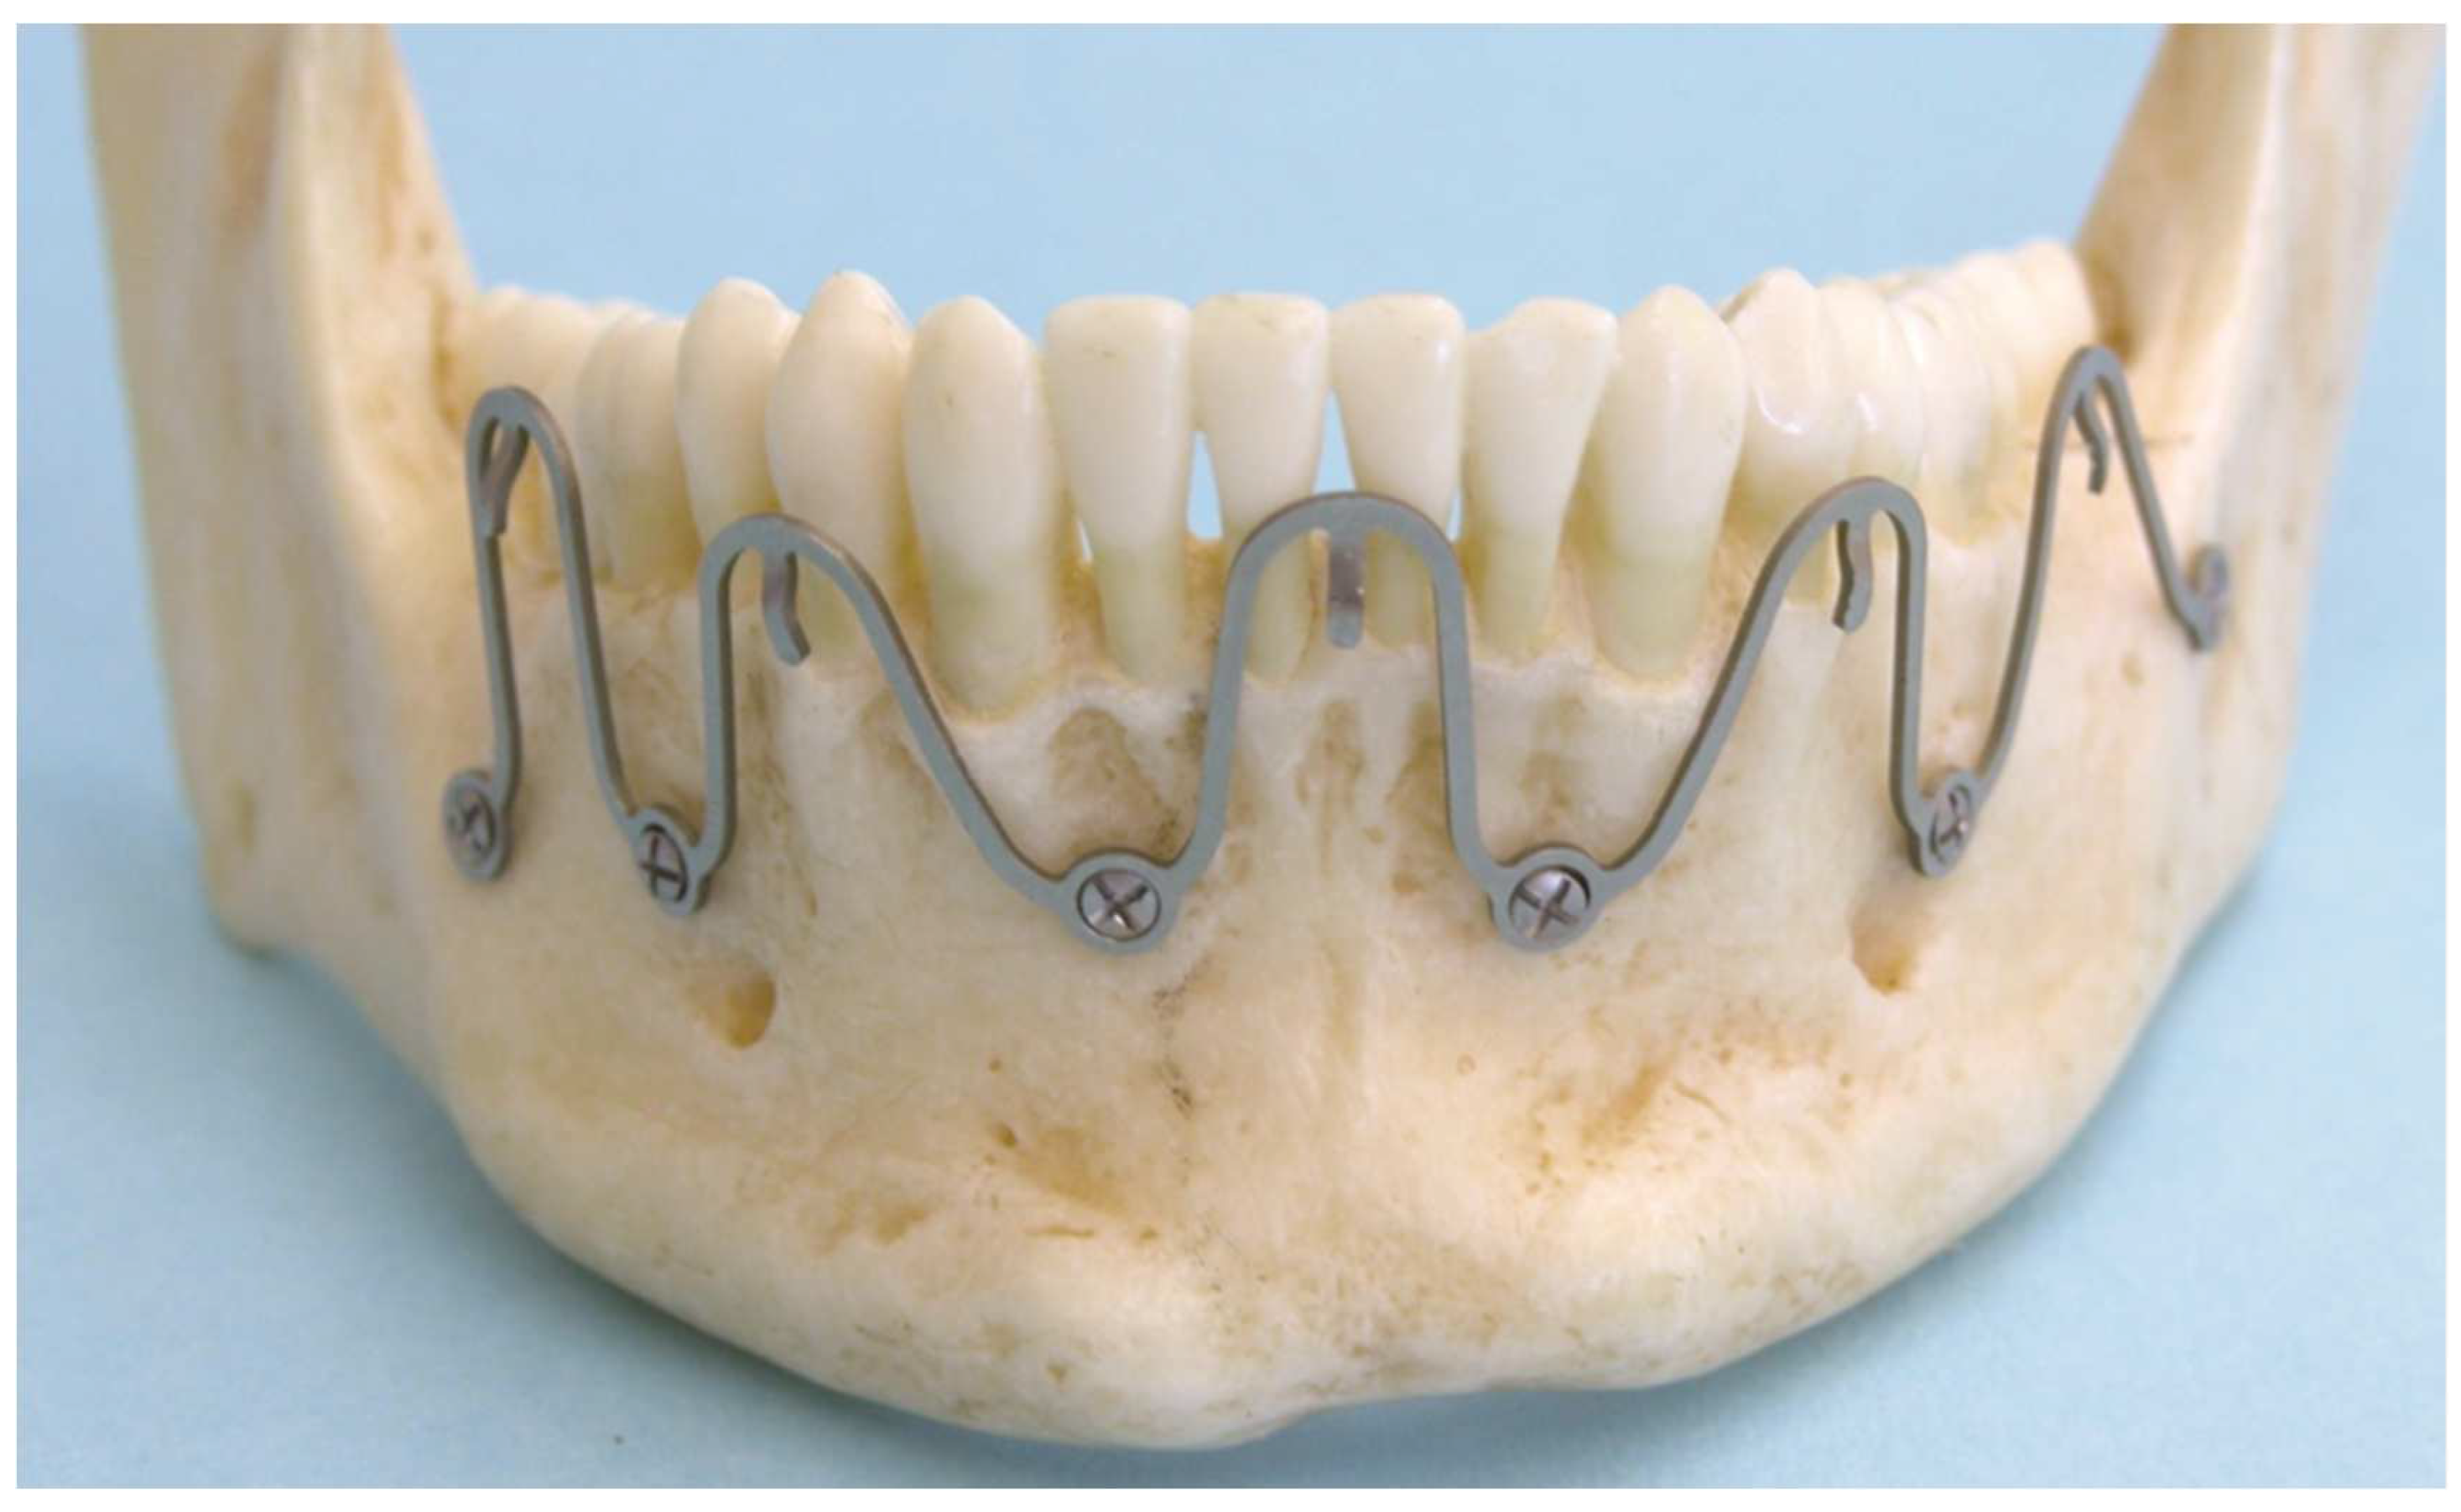

Figure 5.

5 segment wave “plate” prototype mounted on a plastic mandible model. Note: bell curve shape of single wave segments. Median wave segment bell shape unaltered with screw fixation sites between interradicular spaces of lateral incisors and canines. Paramedian and posterior left body wave segments stretched out to reach into subapical zone for screw placement. Posterior right body segment compressed to omit tooth root contact. Wave “plate” crests with wire hooks at slightly varying height adjacent to tooth equator levels. Source/origin of Figure 5: Photograph collection – C.P. Cornelius.